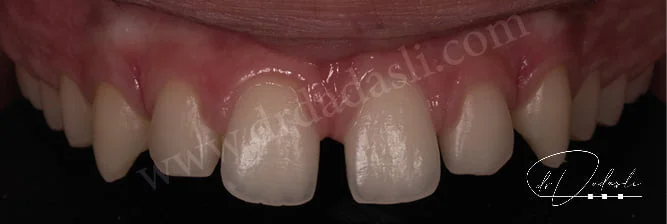

- Üst dişlerinizin önde olması (Şekil 1) – bu durumun iki farklı nedeni vardır: 1) üst dişleriniz öndedir, 2) alt çeneniz veya dişleriniz geride konumlanmıştır. Bu durumun ortodonti bilimindeki ismi Sınıf II maloklüzyondur.